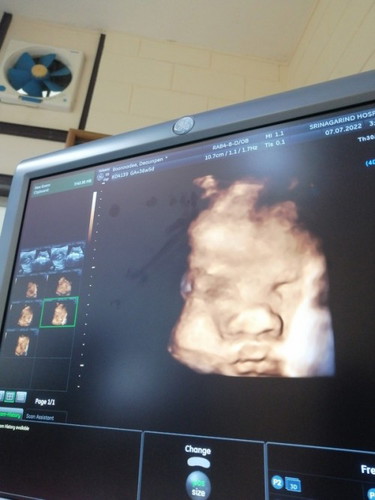

อัลตราซาวด์3มิติเมื่อวานนี้ค่ะ น้ำหนักน้อง3, 400 พึ่ง36+6 น้องตัวใหญ่ไปไหมคะ😅

3,400ถือว่า นน น้องเยอะพอสมควรเลยค่ะ หลังคลอดน้องออกมาน้ำหนักจักเพิ่มขึ้นกว่าในซาวด์ บ้านนี้ซาวด์ได้3,185หลังคลอดน้องนน.3,440เลยย

บ้านนี้เเม่ซาวด์ตอน 36W พอดีค่ะ เต็มท้องเกือบไม่เห็นหน้าน้อง น้ำหนักตอนซาวด์กะตอนคลอดส่วนมากจะไม่ค่อยตรงกันค่ะแม่